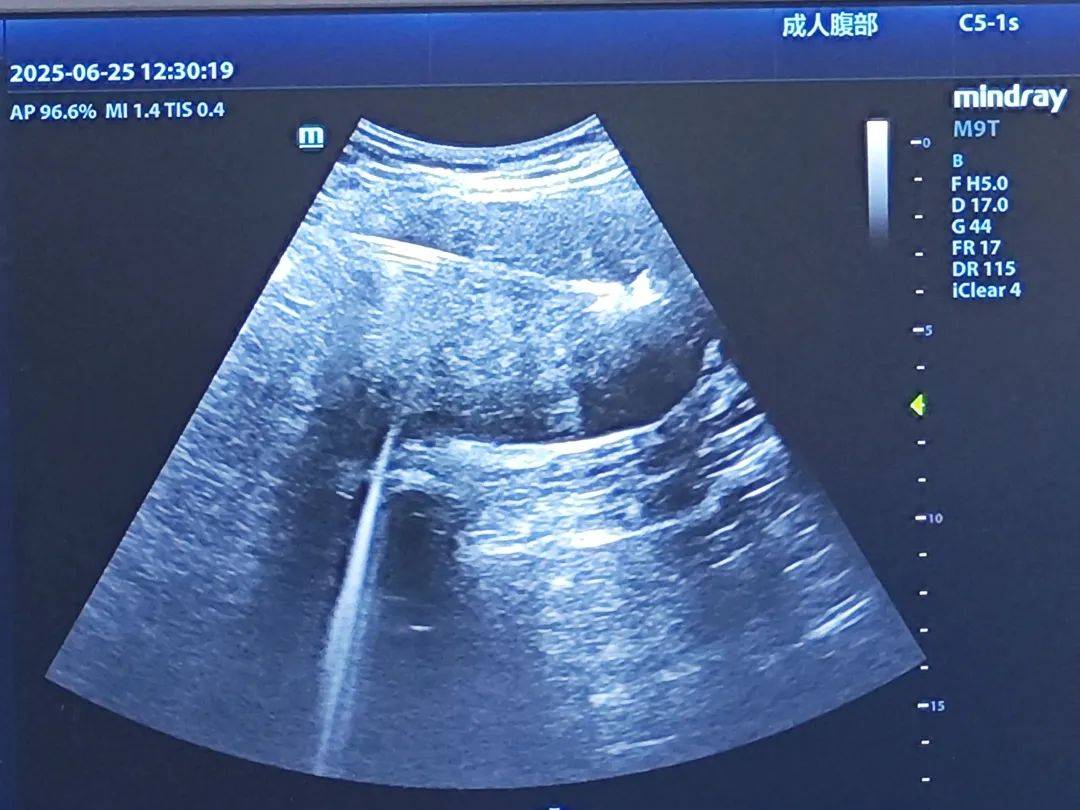

经过一系列严谨的术前检查,曹主任带领团队为汪女士实施了超声引导下经皮子宫肌瘤微波消融术, 在超声的精准导航下,肌瘤被逐一“击破”。